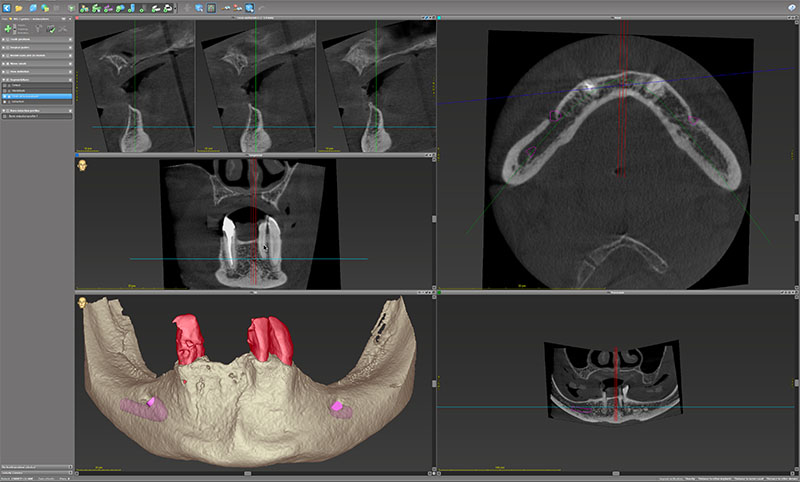

Les fichiers STL issus de l’étude préimplantaire et DICOM en provenance de la CBCT sont implémentés et fusionnés dans le logiciel de planification implantaire coDiagnostiX et donnent naissance à un modèle 3D complexe empilant toutes les données : os, dents, tissus mous, prothèse diagnostique.

Fig. 10 : l’interface plutôt classique de coDiagnostiX 10 avec les différents volets de visualisation. En bas à gauche, la fenêtre de la reconstruction 3D montre l’os (en beige) et la segmentation des dents (en rouge) issus des fichiers DICOM de la CBCT.

Fig. 11 : mise en évidence des alvéoles.

Cette segmentation par seuillage permet d’extraire virtuellement les dents et mettre en évidence les alvéoles.

Fig. 12, 13 et 14 : le rendu surfacique de la numérisation au format STL de l’empreinte secondaire, la prothèse diagnostique et l’antagoniste.

Sur les données DICOM, sont empilés le rendu surfacique de la numérisation au format STL de l’empreinte secondaire, la prothèse diagnostique et l’antagoniste. Ce dernier est la numérisation du montage directeur polymérisé en prothèse complète conventionnelle.

Fig. 15.

Les implants (Neodent GM Helix Acqua, Straumann Group) et les piliers (Mini GM) sont planifiés selon la prothèse diagnostique validée à l’essayage (fig. 15).